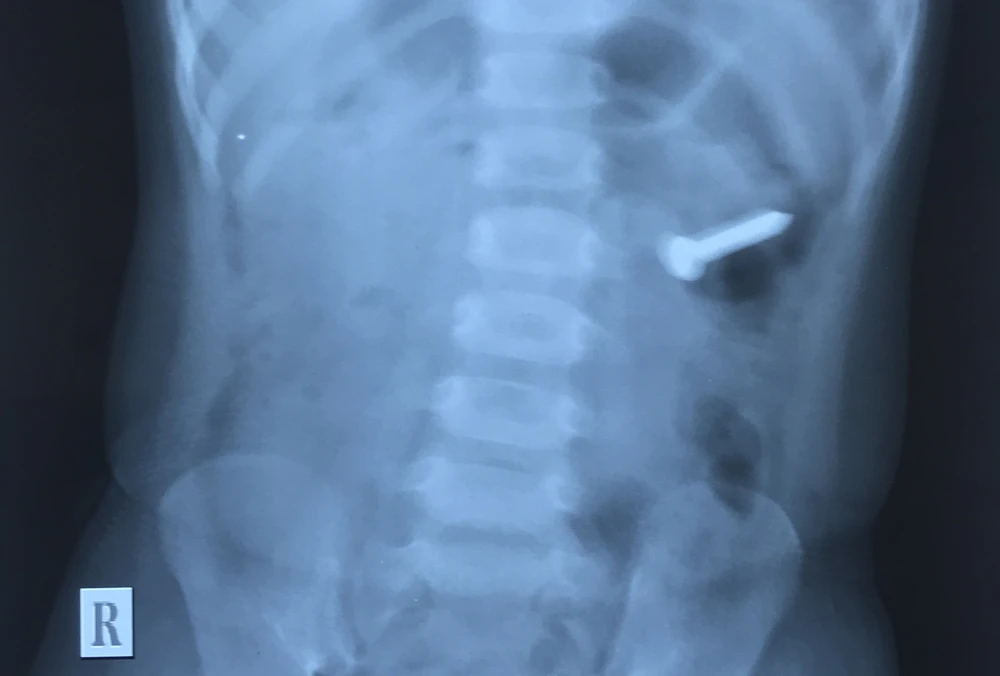

Kết quả chụp X-quang cho thấy chiếc đinh xoắn nằm trong dạ dày bé U. Ảnh: BV Quốc tế Vinh

Kết quả chụp X-quang cho thấy một dị vật cản quang nằm trong dạ dày. Sau đó, các bác sĩ (BS) hội chẩn và tiến hành nội soi gây mê để lấy dị vật ra ngoài.